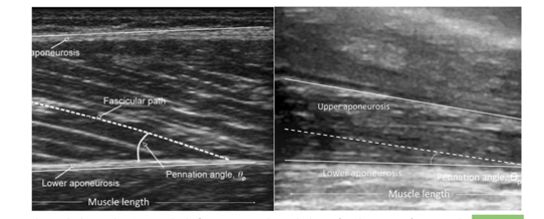

PENNATION ANGLE 羽状角

肌肉纤维和腱膜所成角度。

羽状角大小代表肌力,角度越大,肌肉容积越大,肌肉收缩力越大。